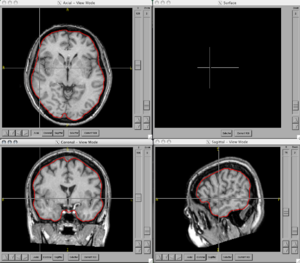

BRAINSCut is a software package for segmentation of structures using artificial neural networks. Currently this tool supports the segmentation of the following structures: brain, caudate, putamen, thalamus, hippocampus, anterior cerebellum, interior posterior cerebellum, superior posterior cerebellum, corpus medullary. Future regions will include the globus pallidus, amygdala, and nucleus accumbens. The command line uses the Slicer3 execution model framework.

Figures

- BRAINSCut